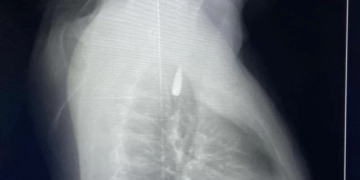

وأوضح الدكتور تامر عبد الله، عميد كلية الطب ورئيس مجلس إدارة المستشفيات الجامعية، أنه في يوم 21 أكتوبر 2025 تمكن فريق من أطباء قسم جراحة القلب والصدر والتخدير والمعاونين من إجراء جراحة دقيقة بالغة الخطورة لأحد المرضى المحجوزين من قطاع غزة، والذي كان قد تعرض لإصابة بطلق ناري في الرأس منذ فترة، استقر المقذوف على إثرها داخل تجويف القفص الصدري قرب الشريان الأورطي، وهو أكبر وأهم شرايين الجسم والمسؤول عن تغذية جميع الأعضاء الحيوية، وأضاف أن الفريق الطبي، رغم دقة الحالة وتعقيدها، نجح في استخراج المقذوف بأمان بعد عملية جراحية نادرة استمرت عدة ساعات داخل المستشفى الجامعي الجديد، حيث خضع المريض بعدها للرعاية الطبية اللازمة، وحالته حاليًا مستقرة وتحت المتابعة الدقيقة من الفريق المختص.